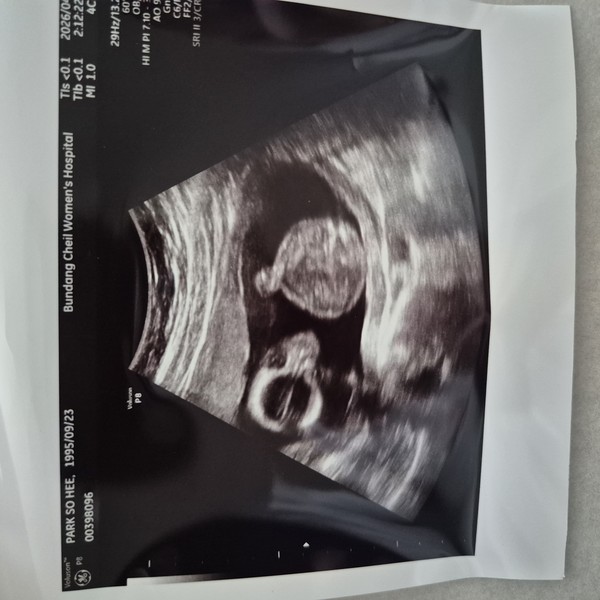

우리의 첫 아기를 기다리며

새 생명의 기쁨

결혼 1주년을 맞아 우리의 사랑이 이루어낸 가장 소중한 기적이 찾아왔어요. 아기의 심장 소리를 듣는 그날, 온 세상이 다 우리를 위해 춤을 추는 듯한 기쁨에 가슴이 벅차 올랐습니다. 아이를 품에 안을 그날을 상상하면, 우리의 작은 세상이 더욱 따뜻하고 빛나는 희망으로 가득 차네요.

It's a Girl

우리의 예쁜 딸이 오고 있어요

아기의 심장 소리

처음으로 듣게 된 작은 심장 소리, 온 세상이 멈춘 듯한 순간

우리의 딸

작은 공주님이 오신다는 소식, 세상에서 가장 달콤한 축복